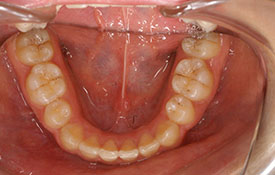

| プロフィール | 15歳 男性 |

| 所見 | アメリカから転院されて来られた方です。 インビザラインで上下顎の矯正治療を開始し下顎はアメリカで終了しており、上顎のみ治療の後期を担当しました。 アイライナーの装着は、1日平均22時間ほどでした。 |